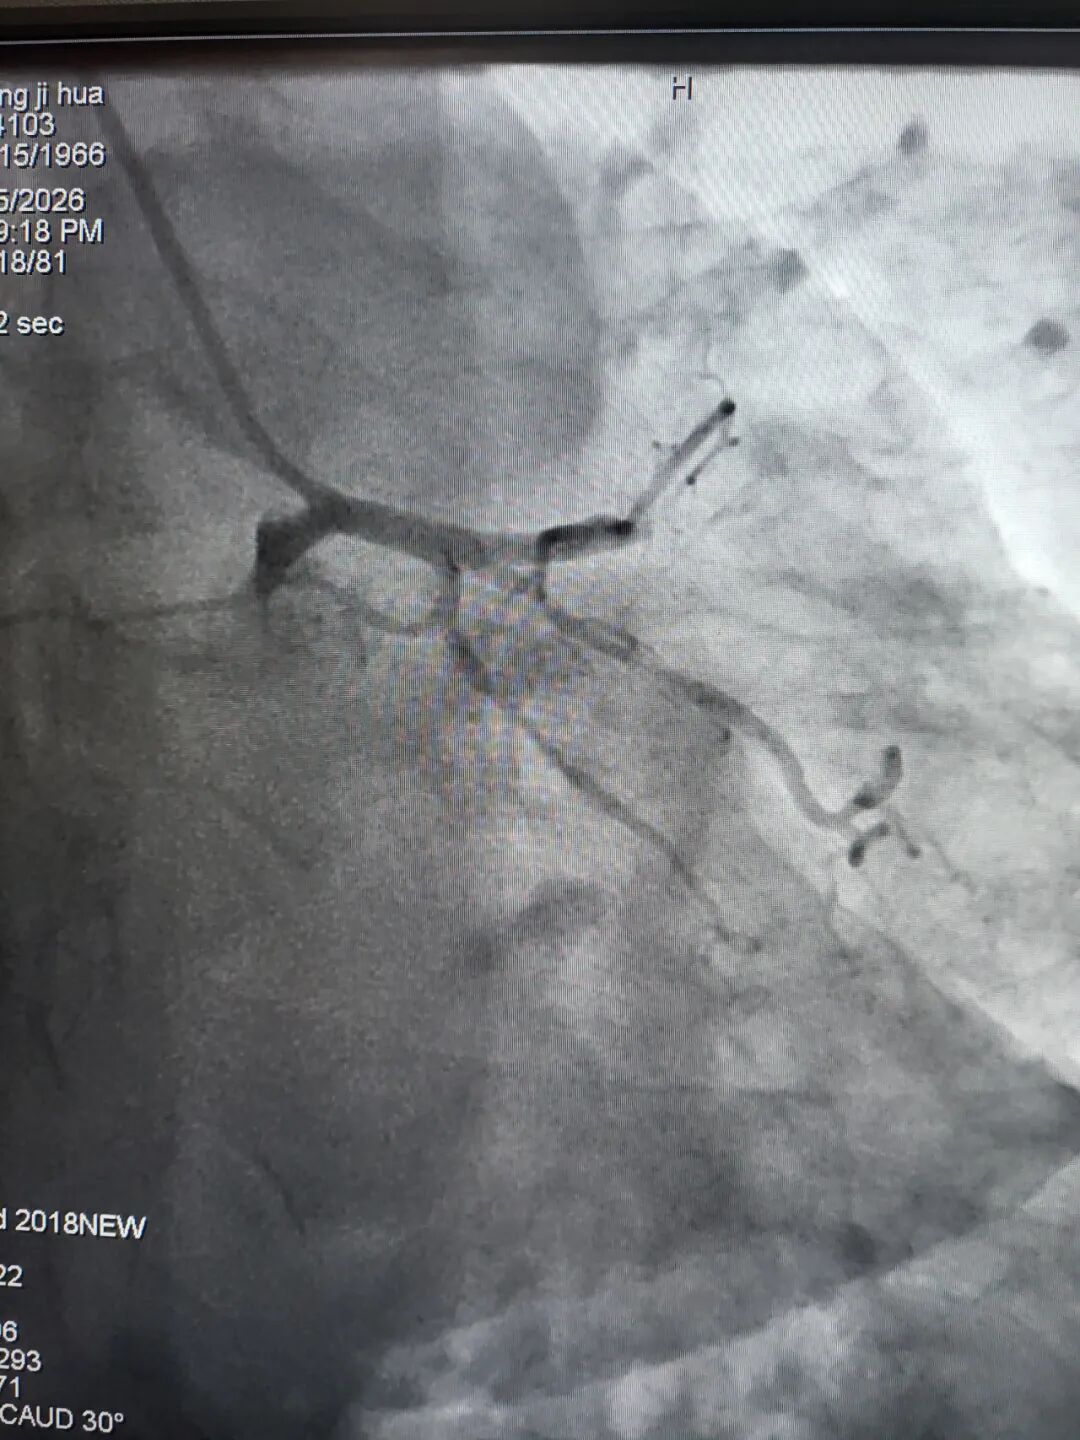

左前降支近中段CTO

右冠近段狭窄99%

左前降支近段狭窄99%

右冠近段次全闭塞

左前降支近中段弥漫性严重狭窄